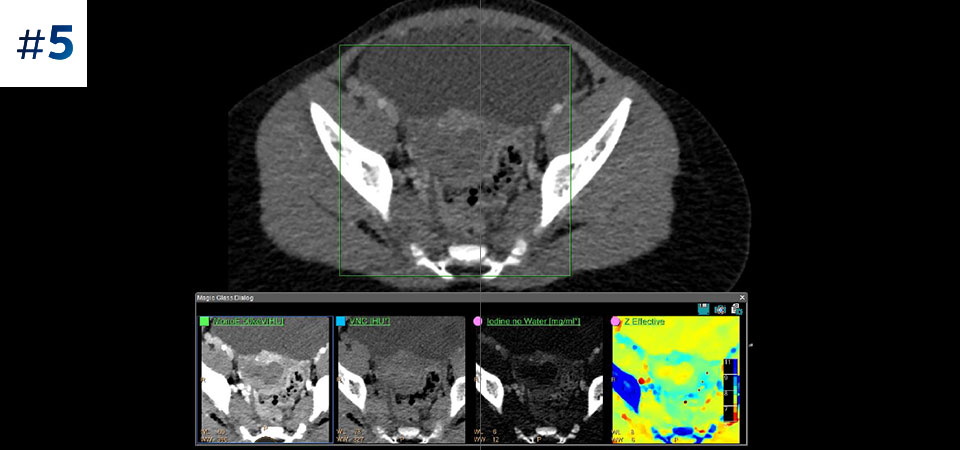

Większe możliwości w zakresie badań kardiologicznych dzięki obrazowaniu spektralnemu pełnego pola widzenia. Redukcja artefaktów powodowanych przez uwapnienie tętnic wieńcowych.

Nie ograniczaj się do konwencjonalnej tomografii komputerowej. Zobacz, jak wyniki uzyskane dzięki warstwom detektora spektralnego mogą zwiększyć pewność diagnostyczną.

Zobacz różnicę pomiędzy tomografią komputerową opartą na detektorze spektralnym a konwencjonalną tomografią komputerową